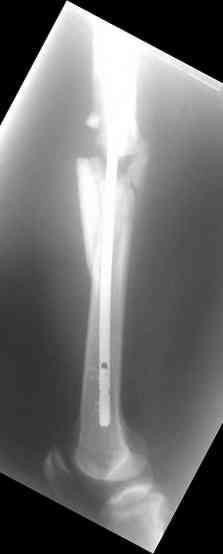

Re: С3-перелом бедра как лечить дальше?....

Dmitry Katritsa 25 Сентябрь 2007, 20:56

одна проблема в моей компьютерной неграмотности(не смог прикрепить снимки), а другая в том, что связь с пациентом потеряна и,насколько я понял в своем регионе ему посоветоваться не с кем, кроме главного врача который отреагировал на выбранную нами тактику так: "там тебя использовали в качестве подопытного кролика...".

Надеюсь сейчас показать перелом, а потом синтез.